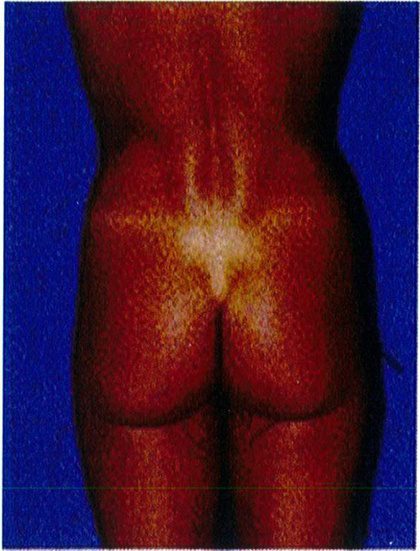

Phân loại này được áp dụng khi có vùng da sa xuống dưới nếp lắn mông và chúng được chia thành 3 giai đoạn I, II, III (Hình 28).

Giai đoạn I

GĐ I rất giống với phân loại không sa – lớp C; tuy nhiên, một phần thể tích mông và da sa xuống dưới nếp lằn mông (mức độ ít). Khi nhìn nghiêng, sẽ phát hiện 1 nếp lằn rõ nằm ngang. Trong những trường hợp này, chỉ cần làm đầy mông mà không cần nâng mông trên.

Ở một nhóm rất nhỏ bệnh nhân có sa mông giai đoạn I, việc cắt bỏ vùng da thừa dưới nếp lằn mông có thể được xem xét nhưng việc thực hiện chúng cực kỳ hiếm khi xảy ra. Các tác giả khuyên nên thực hiện làm đây trước và sau đó đánh giá lại vùng mông sau khoảng 3-6 tháng.

(Hình 28). Ở đây cũng có thể xuất hiện tình trạng mất đàn hồi da và xuất hiện các vết rạn da. Nếu các vết rạn xuất hiện ở khu vực điểm B và C thì nên chỉ định nâng mông; tuy nhiên, đa số trường hợp giai đoạn II chỉ cần làm đầy mông là đủ. Những bệnh nhân này cũng có thể phải cắt bỏ phần da thừa ở gần nếp lẵn mông. Nhưng tác giả khu- yến nghị là nên thực hiện làm đầy mông trước và sau đó đợi từ 3 tới 6 tháng để xem liệu có cần cắt bỏ vùng da thừa đó hay không.

Giai đoạn II

Bệnh nhân ở giai đoạn II, nếp lằn mông vẫn còn nhìn thấy nhưng có tổ chức da sa xuống dưới nếp lắn. Trong khi nếp lắn mông ở giai đoạn I còn nằm ngang thì giai đoạn Il có góc cạnh hơn. Cụ thể, thường có một độ lõm nhất định ở phần trên của vùng mông dưới

Bệnh nhân ở giai đoạn này có phần da chùng nhiều nhất, xuống dưới nếp lằn mông khi nhìn từ phía

của từng đơn vị thẩm mỹ vùng mông sẽ giúp xác định những khu vực nào cần làm đầy/hút mỡ/cắt bỏ hoặc đặt đường rạch.

bên. Nếp lằn này mở rộng về phía mặt trong đùi, và góc tạo bởi chúng và đường liên mông thường lớn hơn 30°. Giai đoạn này cũng được mô tả bởi chỗ lõm ở phân dưới của khu vực trung tâm (hình 28). Các vết rạn da xuất hiện chủ yếu ở vùng điểm B, và da có độ đàn hồi kém với các vết rạn rải rác. Điều trị bệnh nhân ở giai đoạn này cần thực hiện nâng mông trên, cắt vùng da thừa dưới nếp lằn mông và làm đầy mông. Trong các thủ thuật này, có thể thực hiện 1 trong 3 trước đều được.

Ptosis Grade I 0°-10°: Sa mông GĐ 1 0°-10° Ptosis Grade II 10º-30º Ptosis Grade III 30° or greater: Sa mông GĐ III 30° hoặc hơn

Ptosis Grade II 10°- 30°

Hình. 28. Giai đoạn I, II, III của bệnh nhân có tình trạng sa mông. Ở giai đoạn I, góc tạo bởi nếp da nhỏ hơn 10 độ. Ở giai đoạn II, focs này rơi vào khoảng từ 10- 30 độ. Còn ở giai đoan III, góc tao bởi nếp da lớn hơn 30 đô.